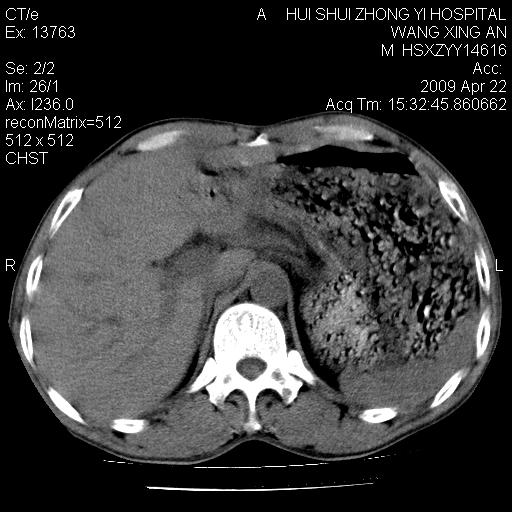

标题: CT19534:患者男、46岁咳嗽、胸痛半月。 [打印本页]

标题: CT19534:患者男、46岁咳嗽、胸痛半月。

考虑---右肺中心型肺癌继发下叶不张,少量胸水。

支持右侧中央型肺ca并右下肺不张、右侧胸腔少量积液。

1、右下肺中央型肺癌并右肺转移,右肺下叶不张。(右肺有结节影)。

2、右中上肺陈旧性肺结核(因为大多为纤维灶)。

3、右侧胸腔积液。

1、右下肺中央型肺癌并右肺转移,右肺下叶不张。(肿块围绕右肺下叶支气管生长,致管腔闭塞右肺下叶不张;右肺有结节影)。

2、右侧胸腔积液。

3、右中上肺陈旧性肺结核(右肺见纤维化病灶及点状钙化)。

1、右下肺中央型肺癌并右肺转移,右肺中下叶不张。(右肺有结节影)。胸骨转移

1)右肺中间段支气管癌并右肺下叶肺不张。2)右肺上叶、两肺下叶背段感染性病变。3)右侧少量胸腔积液。